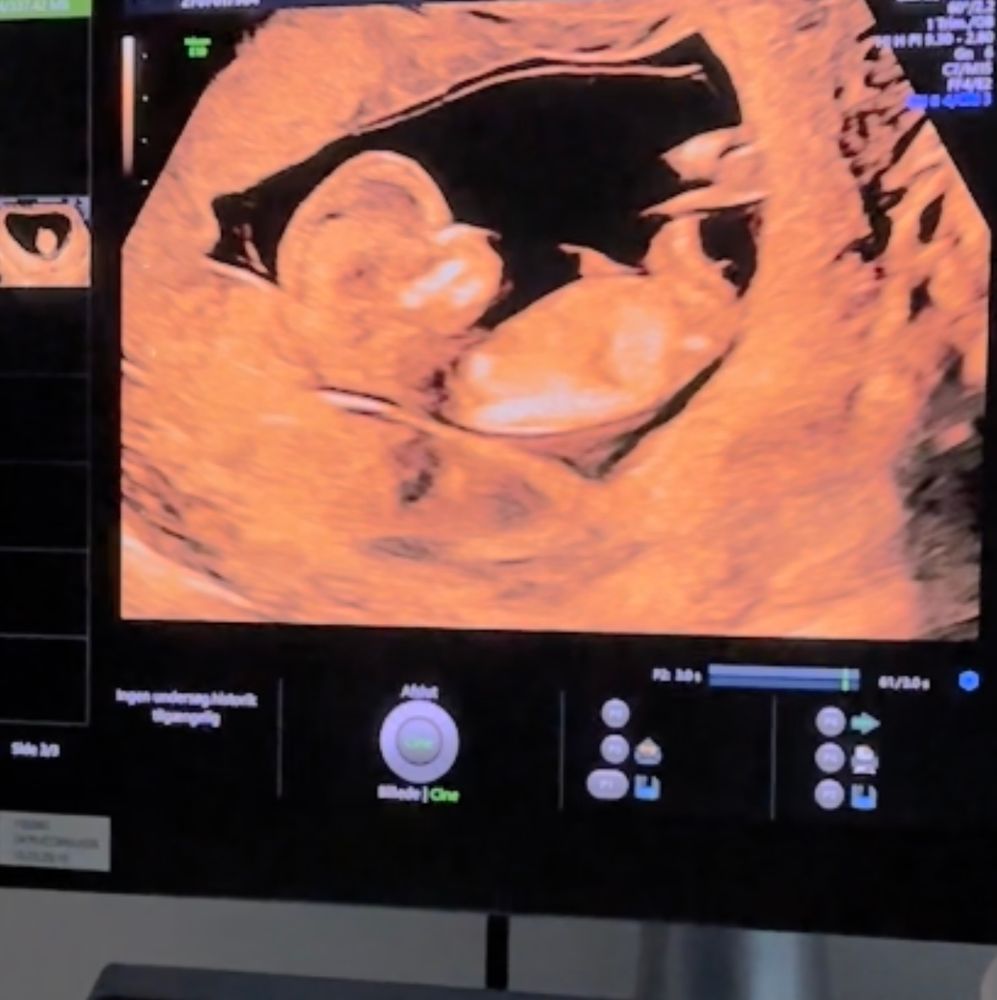

УЗИ 12 недель 😍

УЗИ, КТГ, доплерПривет всем! Сегодня ходила на первый скрининг 💕 здоровенькие и все хорошо 🙏❤️

Не могу разобраться где у малыша половой бугорок, я так понимаю он скрестил ноги. И периодически прыгал. Но есть скриншоты с видео.

Публикую для голосования, кто там 😅❤️